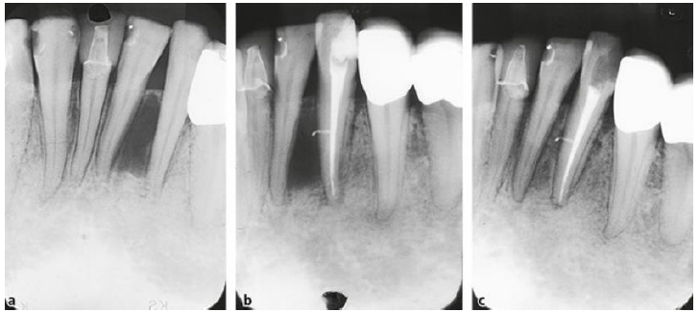

Ao observar a imagem radiográfica marque qual das alternativas está incorreta: